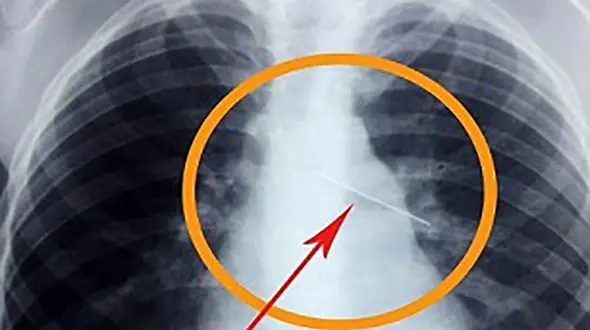

رکنا: سوزن 4 سانتی که با جاخوش کردن در کبد نوزاد 11 ماهه ای جان وی را به خطر انداخته بود با جراحی ویژه ای در قشم خارج شد.